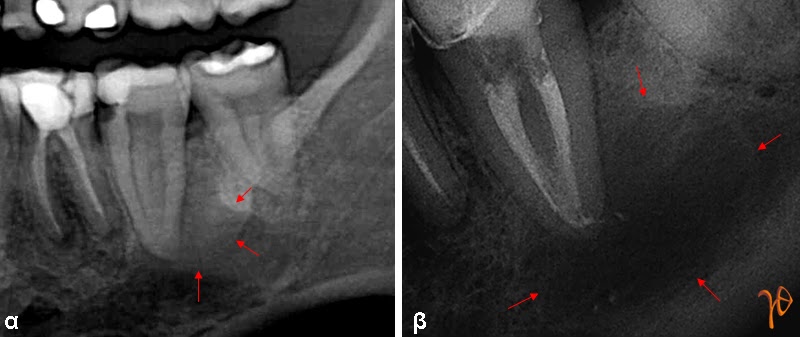

Εικόνα 1: α) Ακρορριζική βλάβη # 37(βέλη), β) Ένα χρόνο μετά την ενδοδοντική θεραπεία, η αλλοίωση έχει επεκταθεί (βέλη)